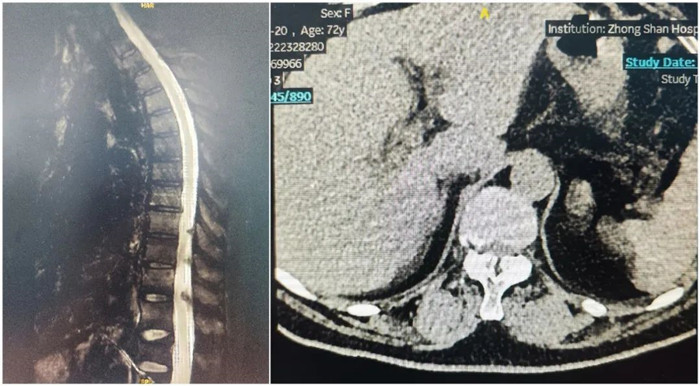

患者兩年前出現左側胸背部皮膚感覺麻木,有束帶感,左上臂皮膚感覺麻木,否認肌力減退,胸平掃椎CT示:胸椎序列正常,生理彎曲存在,椎體邊緣骨質增生,椎間盤略退變,T7-T9黃韌帶增生并伴骨化,壓迫內膜囊,椎管狹窄。影像診斷:黃韌帶骨化。

術前影像

普愛醫療術中三維導航C臂快速生成橫斷面、矢狀面、冠狀面斷層圖像和三維立體圖像,方便醫生確認手術部位。C形臂的大平板帶來出色的顯示視野,可以更好的顯示手術部位全局情況,確保手術規劃及執行的準確性。